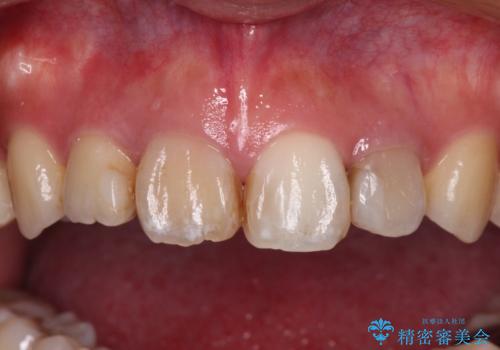

- 八重歯と前歯のデコボコ、開咬を気にして来院された患者様です。

上顎前歯や下顎大臼歯に根管治療の必要な歯がいくつかあるため、矯正治療と並行して根管治療を行い、その後オールセラミッククラウンにて補綴治療を行うこととしました。